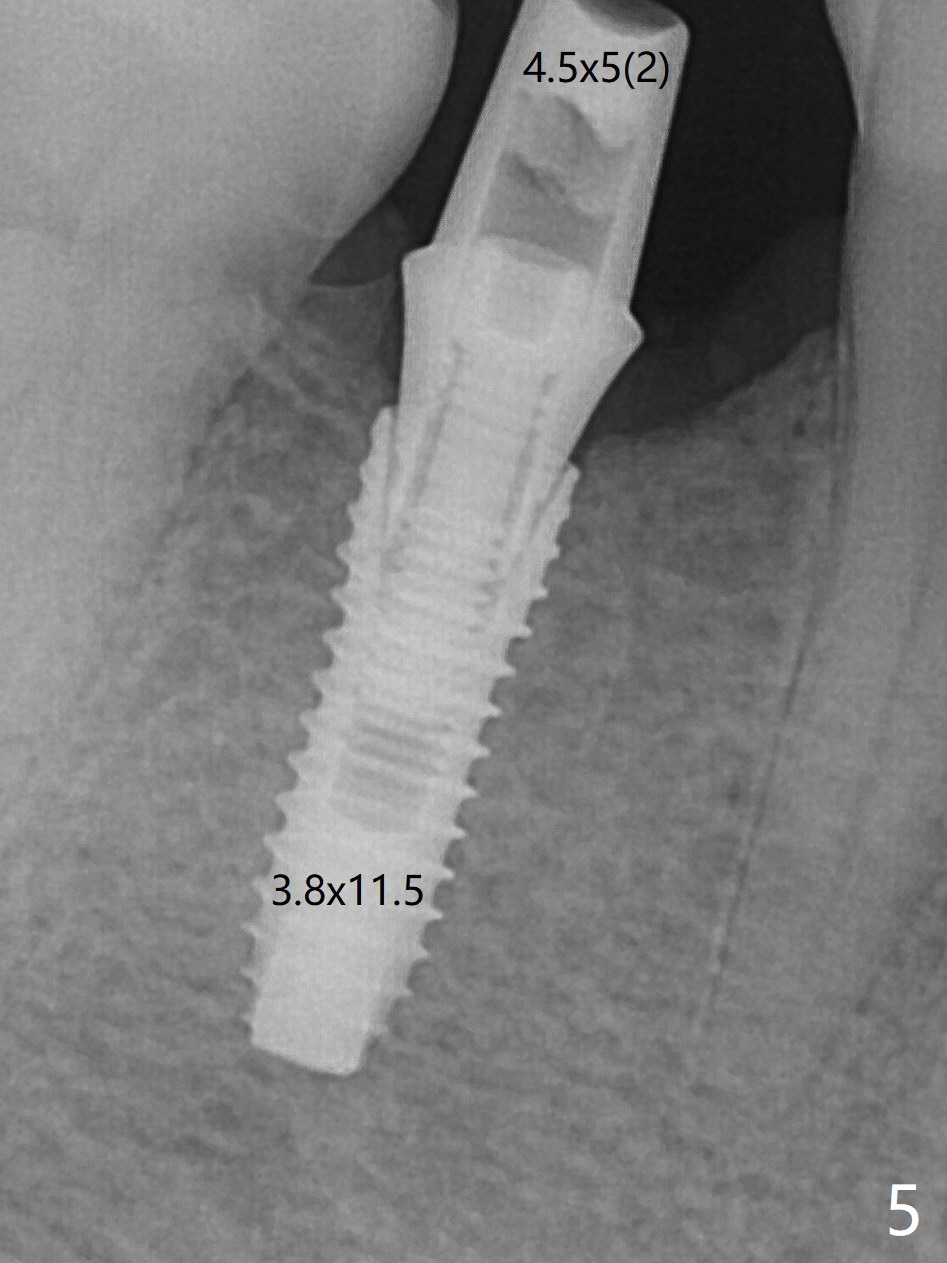

Although the final depth of osteotomy is 13 mm, the implant placed is short (3.8x11.5 mm, Fig.5,6), as compared to the immediate implant (3.8x18 mm) at the contralateral side (#20). There is mild bone resorption mesially 4 months postop (Fig.7).